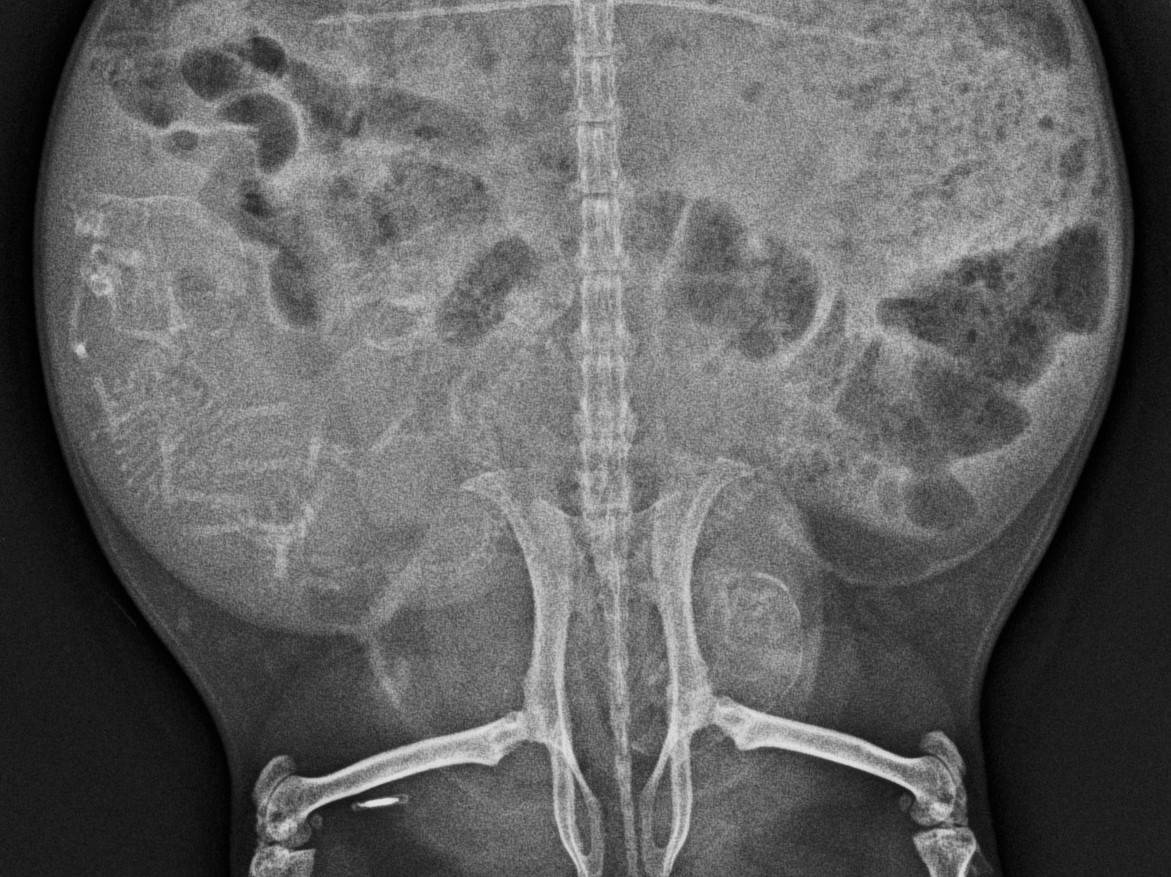

11月下旬のこと、オスと同居させてるメスのモルモット、一茶のお腹が大きくなってきたので、

妊娠してるかも?とレントゲンを撮ることにしました。

そしたら...胎児の骨格がしっかり映っています!3頭の胎児が確認できました!!

モルモットの妊娠期間は60~70日くらいと言われていて、

レントゲンに胎児の骨格が映るようになるのが大体妊娠45日くらいから。

実はこの個体、10月末にも少しお腹が大きくなった気がするとレントゲンを撮っていたのですが、

その時には胎児は確認できていませんでした。

これがその時の写真。上の写真と比べてみて是非胎児の骨格を探してみてください!